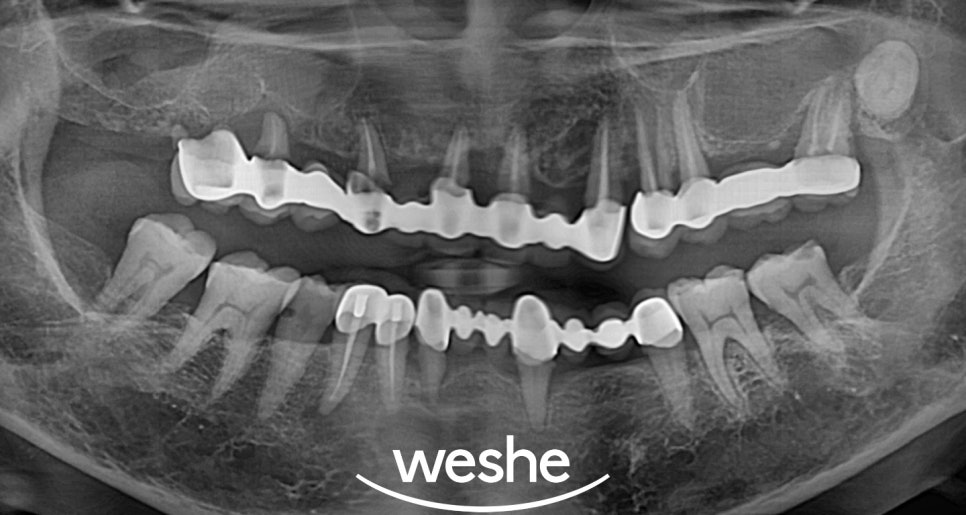

✔ 기본 검사

엑스레이 촬영을 통해 상악의

전체적인 치아와 뼈 상태를 확인합니다.

기존 치아들의 치료 가능성을 평가하고

풀아치 임플란트가 적절한 치료 방법인지

판단합니다.

✔ 최종 보철 완성

최종 보철물은 개별 치아 형태와 색상을

자연치아와 최대한 유사하게 제작합니다.

특히 상악은 웃을 때 잘 보이는 부위이므로

심미성에 특별히 신경을 씁니다.

교합 조정을 통해 위아래 치아가 정확하게

맞물리도록 하여 저작 기능을 완전히

회복시킵니다.